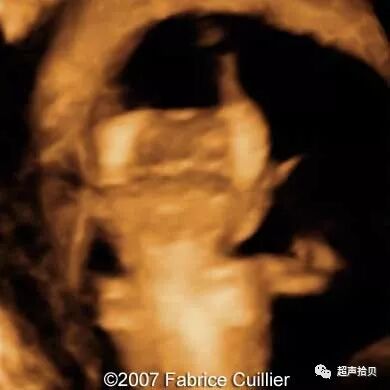

图3胎儿在妊娠25周时从表面到颅骨的三维图像。 A和B,胎儿的表面部分和面部图像。 C和D,胎儿脑部更深的三维切片。 E和F,三维切片显示胎儿脑中的蛛网膜囊肿(箭头)

图4:妊娠26周时的产前MRI:第三脑室蛛网膜囊肿的横向(A),矢状(B)和冠状面(C)平面引起脑室扩张